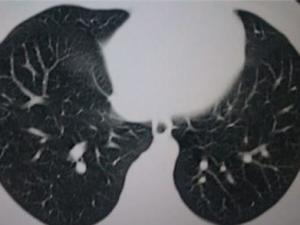

疾病检查

陈旧性肺结核陈旧性肺结核胸片。

诊断鉴别

陈旧性肺结核陈旧性肺结核根据胸片可确诊。